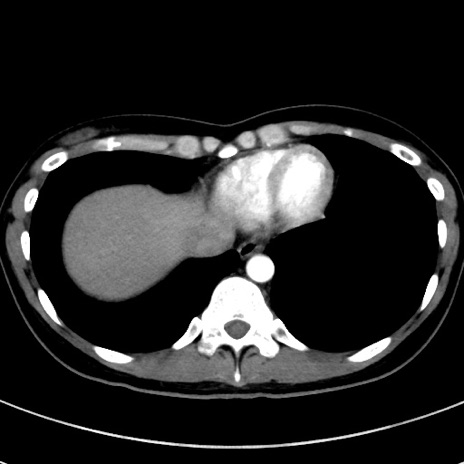

症例17(横断像)

【症例】20歳代女性

【主訴】嘔吐、下腹部痛

【現病歴】昨日夕食後に嘔吐し下腹部痛が出現。本日になっても嘔吐持続し改善しないため来院。

【身体所見】意識清明、BT 37.2℃、BP 108/67mmHg、腹部:平坦、やや硬、下腹部正中から右にかけて圧痛あり、反跳痛軽度あり、tapping pain(+)。

【データ】WBC 13600、CRP 14.94